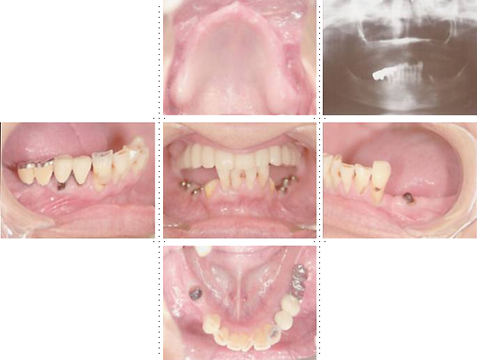

症例4

57才 女性

知人の歯科医からのご紹介。良く噛めない為、元気が出ない。介護の仕事を続けるためにも、歯を治療して自分がもっと元気になりたい。最初は部分的に治療する予定だったのですが、歯のない部分はインプラントを埋入し、最終的には上下顎全ての歯を治療し、しっかりものが噛めるようになりました。